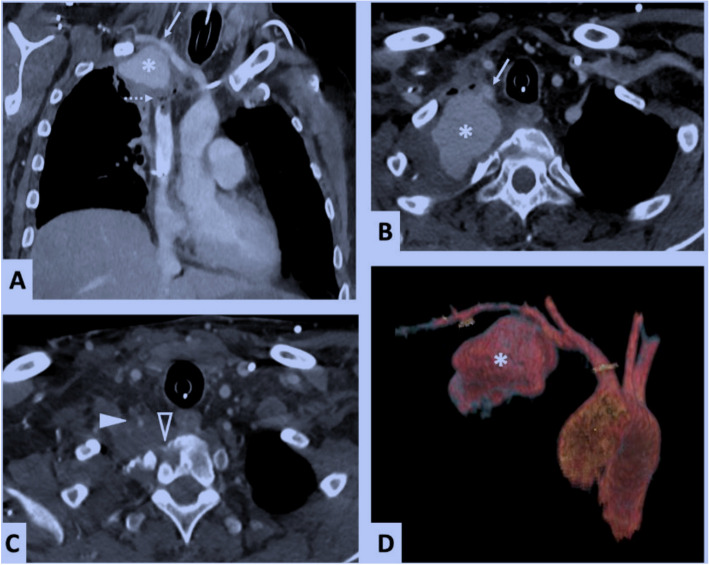

Background: The authors report herein a rare case of an endovascular management of a giant subclavian artery pseudoaneurysm, revealed by a massive hemoptysis in a patient suffering from a Pancoast tumor.

Case presentation: The endovascular procedure consisted of covering the subclavian artery rupture site with a stent graft after occluding the proximal segments of the ipsilateral internal thoracic and vertebral arteries.

Conclusion: Subclavian artery rupture was effectively managed using endovascular techniques via radial access.